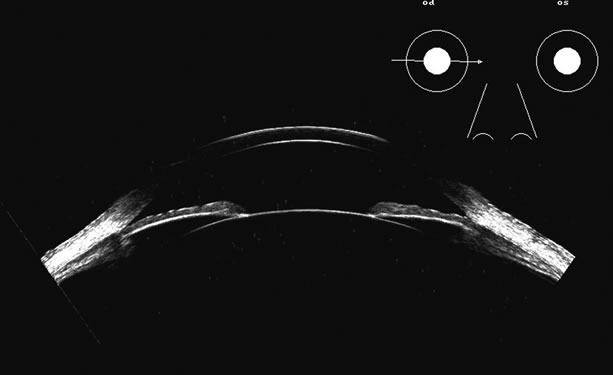

Lens position, presence, and integrity can be shown most easily with immersion ultrasound, since the proximity of these structures to the transducer in contact techniques makes them difficult to display. Immersion or a water standoff makes it possible to visualize the anterior segment by moving the “noise” of the main bang of the transducer forward, away from the structures of interest and the focal zone onto this area.8 The lens is a “specular” reflector which, like the cornea, is a smooth, highly reflective surface. Whereas specular reflectors, such as the lens, may deflect most acoustic energy away from the transducer when insonified at an oblique angle, “diffuse” reflectors, such as blood-covered membranes, are more easily discerned on B-scan. Blood enhances lens boundaries; that is, it converts the specular reflective surface to a diffuse reflective surface, making the entire outline of the surface more easily seen, even at regions angled so they would otherwise deflect the returning echoes away from the transducer and not be identifiable. The posterior capsule is concave and thus perpendicular to the beam over much of the arc of sector B-scanning, thus making it always easy to identify. The lens outline should be smooth and unbroken (Fig. 1); a damaged lens often is cataractous and has internal echoes as well as interrupted surface echoes.9 Kinetic scanning, that is, real-time scanning while the patient moves his or her eye, can be used to check for mobility of the lens in dislocated or partially dislocated lenses.

Fig. 1. Very high frequency ultrasound scan of the anterior segment of the eye. The posterior chamber is easily outlined at this nominal 50 MHz scan as the region posterior to the iris plane. The ciliary body is well defined as is the region at the equatorial margin of the lens. Pathology in this area is of interest to the posterior segment surgeon as it contains several treatable entities, such as foreign bodies, ciliary body tumors, cysts, and separation, as in hypotony.